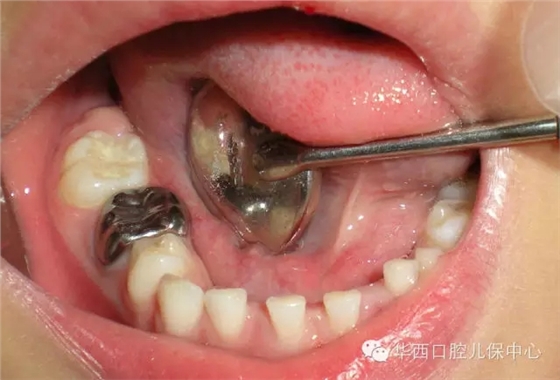

單個乳磨牙齲壞充填后的預(yù)成冠修復(fù)